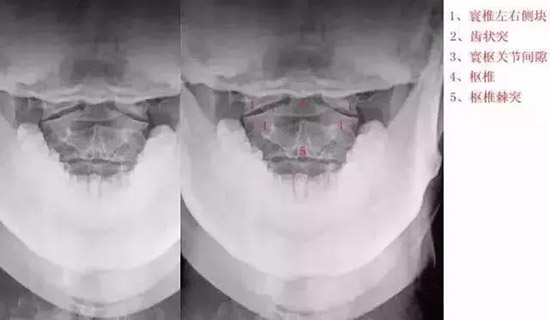

十张口:指观察张口位投照的X线正位片。

(1)观察寰枢椎,

(2)看齿状突,

(3)观察寰椎椎弓,

(4)寰齿关节间隙,

上位颈椎X光片,张口位

1.枢椎之齿突,

2.寰枢之外侧块,

3.寰枢关节,

4.枢椎之椎体,

5.第3颈椎 ,